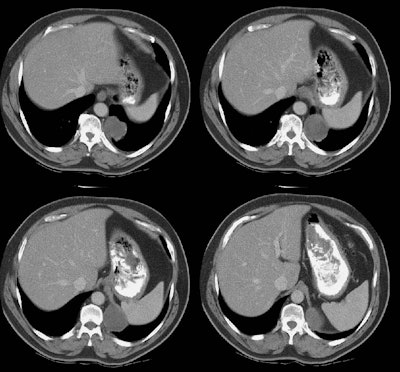

The CT scan demonstrated a low density mass in the left posterior costophrenic sulcus. A percutaneous biopsy was performed and on aspiration material with the consistency of "crank oil" was withdrawn. The fluid contained inflammatory cells, but no organisms. Surgical removal was recommended. Because of the possibility that the lesion may represent a bronchopulmonary sequestration, a pulmonary arteriogram was also performed.

The exam demonstrated no systemic arterial supply to the lesion. At histopathologic analysis the lesion was found to be a bronchogenic cyst.